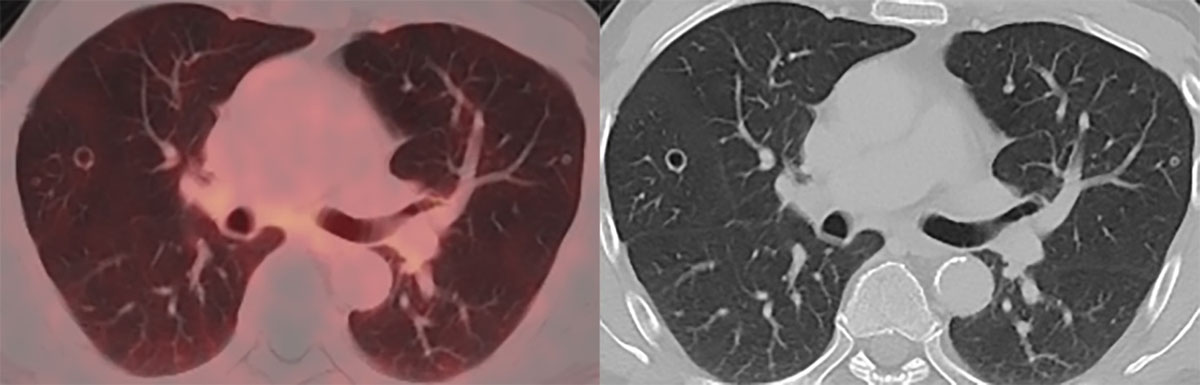

In November 2020, PSA-levels increased to 6 ng/mL and a third follow-up F18-PSMA-PET-CT revealed multiple, thin- and thick-walled, excavated, pericentrimetric, randomly distributed, nodular lung lesions with a slightly metabolic avid wall bilaterally (Figure 1) and enlarged para-iliac lymph nodes. The lymph nodes were treated with three sessions of stereotactic body radiation therapy in January 2021. The lung nodules were not treated, as their metastatic potential was considered low based on their morphology. A fourth F18-PSMA-PET-CT in May 2021 (Figure 2) and a CT-thorax in June 2021 (Figure 3) showed PSMA-uptake and increased volume and number of the cavitary lung nodules. A broad differential diagnosis of vasculitis, granulomatous disease, infectious/septic embolisms and atypical metastases was suggested.

Figure 1